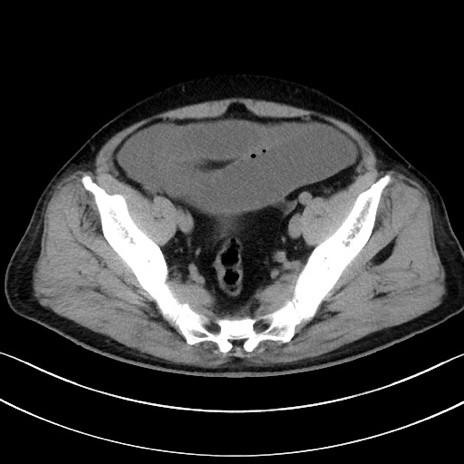

症例15(横断像)

【症例】70歳代男性

【主訴】腹痛

【現病歴】今朝から腹痛あり。全体的に痛い。特に左上の方。排ガスが今日はない。冷や汗が出る。

【既往歴】直腸癌術後

【身体所見】左側腹部〜上腹部に圧痛あり。腹膜刺激症状明らかなではない。軽度反跳痛。左下腹部に術後瘢痕あり。

【データ】WBC 7700、CRP 0.02